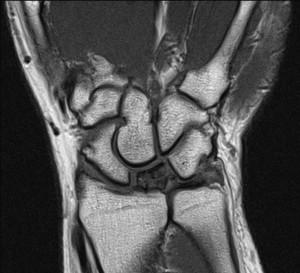

Lunat kemiği el bilek hareketlerini sağlayan ilk sıra kemiklerinin arasında bulunur ve deyim yerindeyse el bileğinin dengesini sağlar. Kienböck hastalığı yarım ay şeklinden dolayı Lunat ismini almış olan bu kemiğin kan dolaşımının bozulması sonucu oluşan hastalıktır. Beslenmesi bozulan kemik zamanla çürümeye ve gücünü kaybederek çökmeye başlar. El bilek üzerine düşme gibi travmalar dolaşımın bozulmasına sebep olabileceği gibi el bilek anatomisinde doğuştan olan bir takım değişikliklerin bu hastalığa sebep olabileceği bildirilmiştir. Özellikle önkolu oluşturan ulna ve Radius isimli kemiklerin el bilek seviyesinde aynı hizada sonlanmaması, özellikle Ulna kemiğinin daha kısa olması Lunat kemik üzerine daha fazla baskı oluşmasına sebep olur. Negatif Ulnar Varyans olarak adlandırılan bu anatomik değişiklik hastalığın sebebplerinden olduğu kabul edilmektedir. Ancak her zaman altta yatan bir patoloji bulunamayabilir.

Kienböck hastalığının cerrahi dışında bilinen bir tedavisi yoktur. Ancak eğer hastalık çok erken evrede yakalanmış ve çekilen MRI görüntüleme sonrasında henüz osteonekrozun (kemik çürümesi) başlamadığı görülürse bir takım önlemler alınabilir. El bilek istirahat ortezi kullanılması, ödem giderici NSAID grubu ilaçların kullanılması ve yüksek basınçlı oksijen bunların arasında sayılabilir. Ancak bu şekilde takip edilen hastalarda sık olarak kontrol edilmeli ve tekrarlanan MRI görüntülemede osteonekrozun başladığı görülür ise cerrahi tedaviye geçilmelidir.